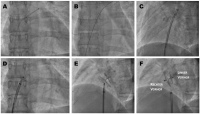

Abbildung 1A-F: Perkutane Implantation eines Amplatzer-PFO-Occluders. A: Aufsuchen des PFO mit einem Multipurpose-Katheter, falls Draht nicht von allein dahin findet; B: Platzieren eines Standard-Drahtes im linken Vorhof; C: Platzieren der Einführungsschleuse im linken Vorhof; D: Freisetzen der linksatrialen Scheibe eines Amplatzer-PFOOccluders; E: Unter Rückzug der Schleuse Freisetzen der rechtsatrialen Scheibe zum Zusammenpressen von Septum primum und Septum secundum; F: Absetzen des Amplatzer-PFO-Occluders.